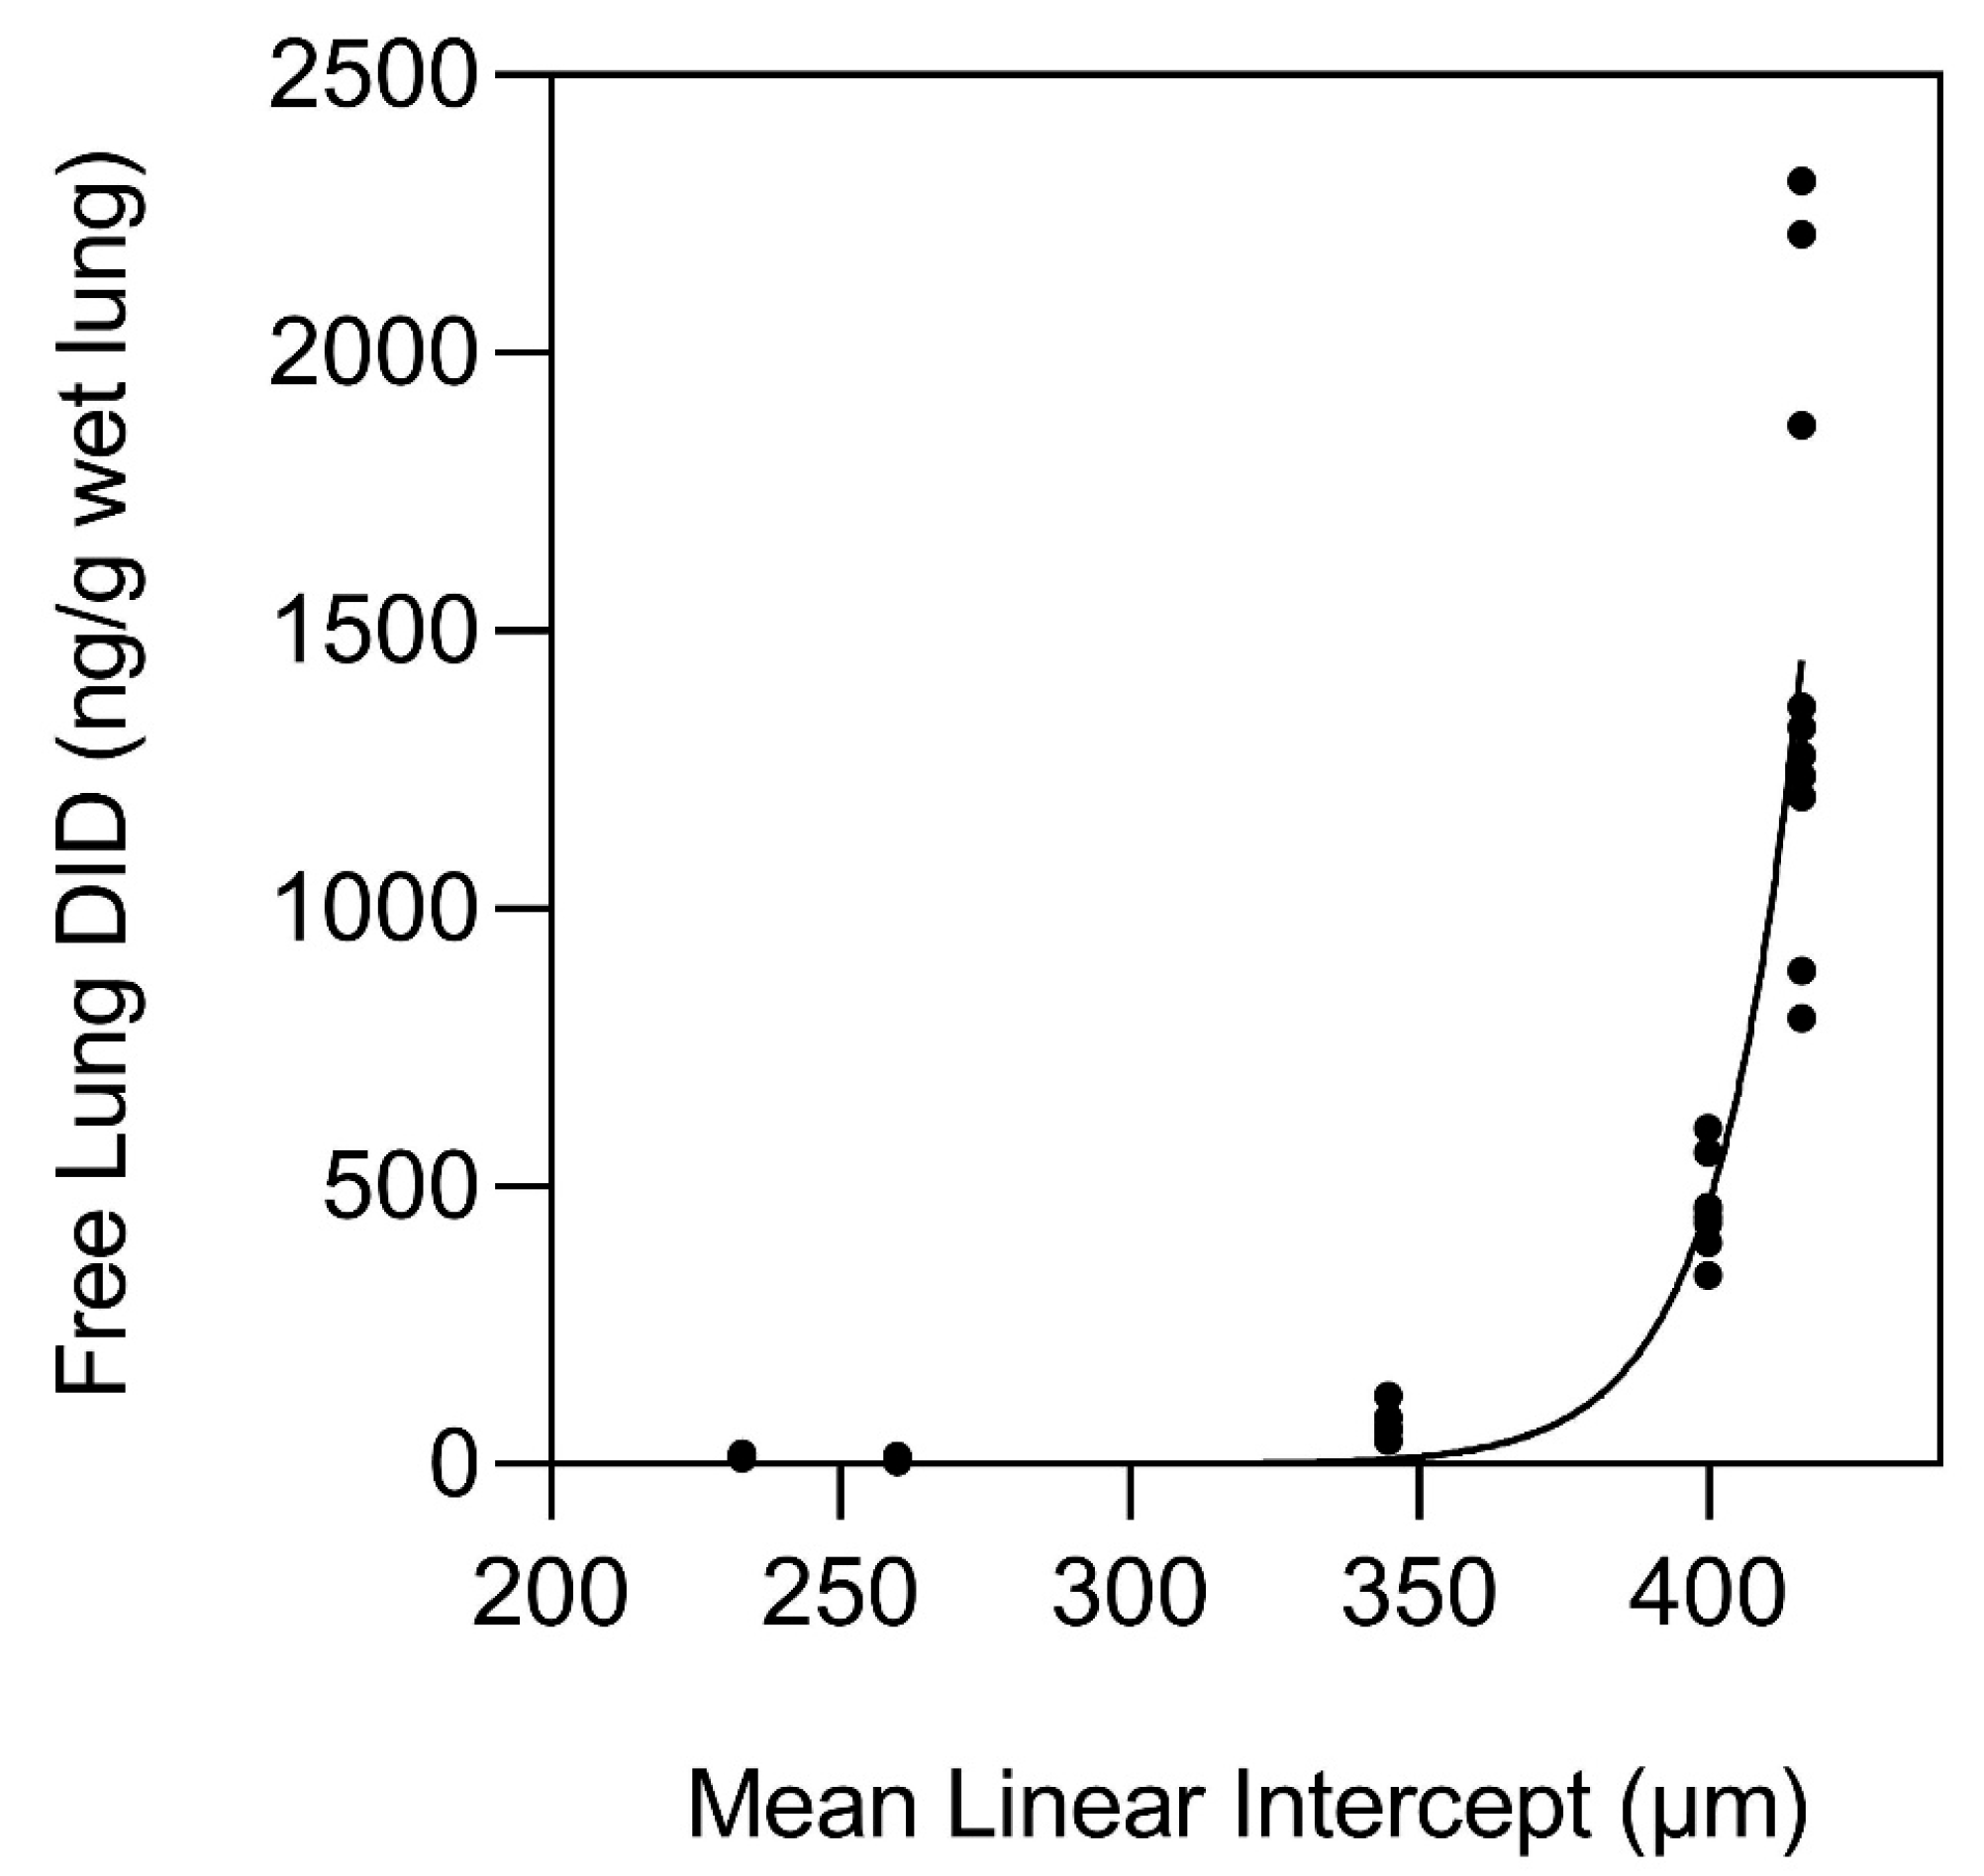

- Fagiola, M.; Reznik, S.; Riaz, M.; Qyang, Y.; Lee, S.; Avella, J.; Turino, G.; Cantor, J. The relationship between elastin cross linking and alveolar wall rupture in human pulmonary emphysema. Am. J. Physiol. Lung Cell Mol. Physiol. 2023, 324, L747–L755. [Google Scholar] [CrossRef] [PubMed]

- Cantor, J. Desmosine as a biomarker for the emergent properties of pulmonary emphysema. Front. Med. 2023, 10, 1322283. [Google Scholar] [CrossRef] [PubMed]